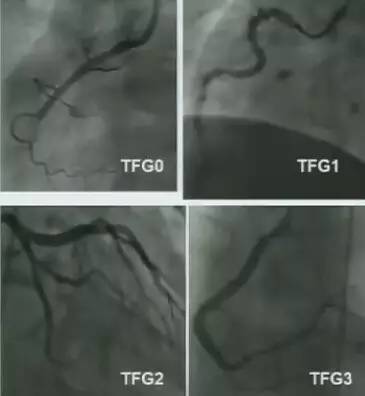

TIMI血流分级:0级:无灌注,闭塞部位及远端无造影剂充盈;1级:造影剂通过闭塞部位,但远端血管无灌注;2级:造影剂可达到远端血管,但充盈速度明显减慢;3级:远端血管充盈快速且完全。

图4 TIMI血流分级(TFG)

TIMI心肌灌注分级(TMPG)代表心肌微循环灌注的情况。有研究发现,TFG和TMPG与死亡率相关,随着TFG和TMPG的降低,患者的死亡率增高。